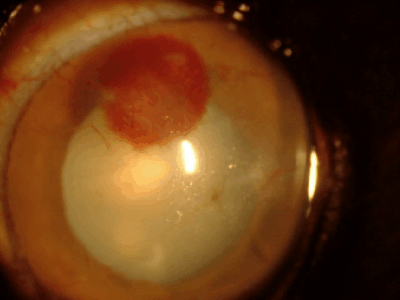

黒目が赤い場合

血管新生

角膜には本来血管がなく透明ですが、炎症、傷、刺激などが慢性化すると角膜周囲から血管が伸びてきます。だいたい1日あたり1mm伸びるといわれています。原因としては角膜炎、角膜潰瘍、乾性角結膜炎(ドライアイ)、パンヌスなどがあります。